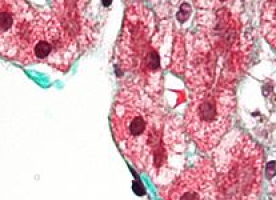

Genetically-induced IDO deficiency reduced lung tumour burden and improved survival in both models.

Analysis of differences between the lungs of IDO-sufficient and -deficient tumour-bearing mice in the KRAS-induced lung carcinoma model revealed that levels of the pro-inflammatory molecule IL-6 were markedly lower in the absence of IDO. Levels of this known tumour-promoting factor were also lower in the model of metastasis when IDO was absent.

Additional work in the model of metastasis indicated that IDO-potentiated IL-6 production and promoted metastasis to the lung by driving the expansion and immunosuppressive function of a population of cells known as myeloid-derived suppressor cells (MDSCs). MDSCs are well-characterised, potent inhibitors of antitumour immune responses.